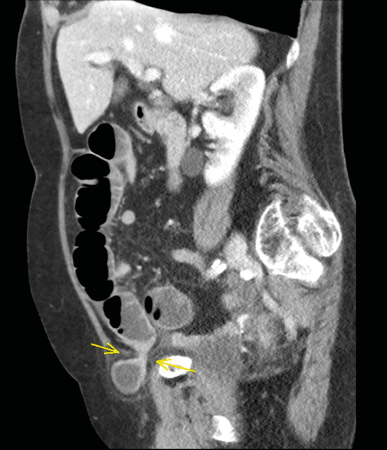

Typisches CT einer inkarzerierten Leistenhernie (Pfeil). Die Einklemmung hat schon zu einem Ileus (Spiegelbildung) geführt. Typisches CT einer inkarzerierten Leistenhernie (Pfeil). Die Einklemmung hat schon zu einem Ileus (Spiegelbildung) geführt. © Albertinen-Krankenhaus Hamburg